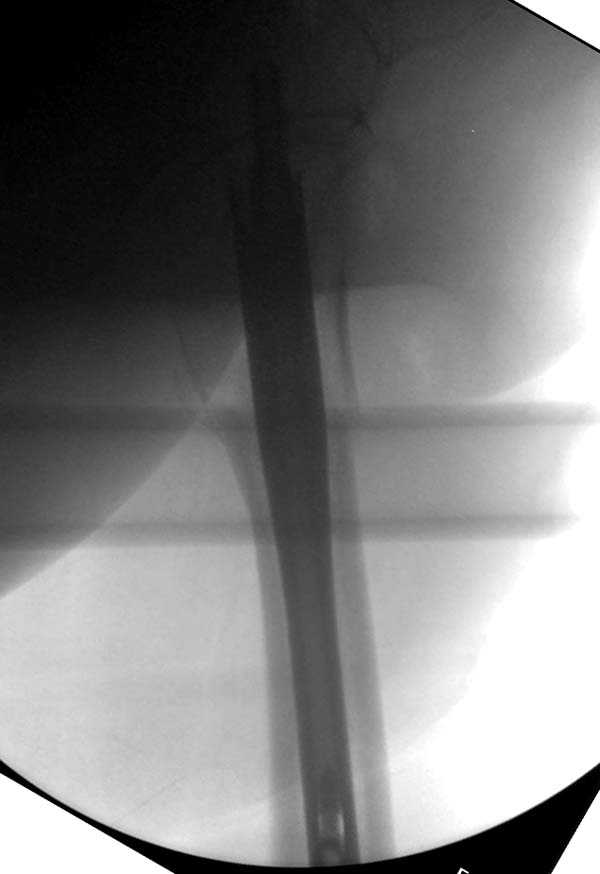

Здесь представлен случай, где в послеоперационном периоде обнаружена техническая ошибка, Gamma 3 установлен с нарушением методики. Больная в 91 лет, прооперирована через день после поступления и выписана через 48 часов.

Считаем, что техническая ошибка произошла во время установки гвоздя, когда рассверливанию канала не уделили должного внимания. Канал остался узковат, и гвоздь был забит с силой. Полная нагрузка конечности приостановлена на две недели, и боли в конечности изчезли. Больная начала нагрузку и перелом срастается.-- Djoldas Kuldjanov, M.D.Associate ProfessorDepartment of Orthopedic SurgerySt. Louis University